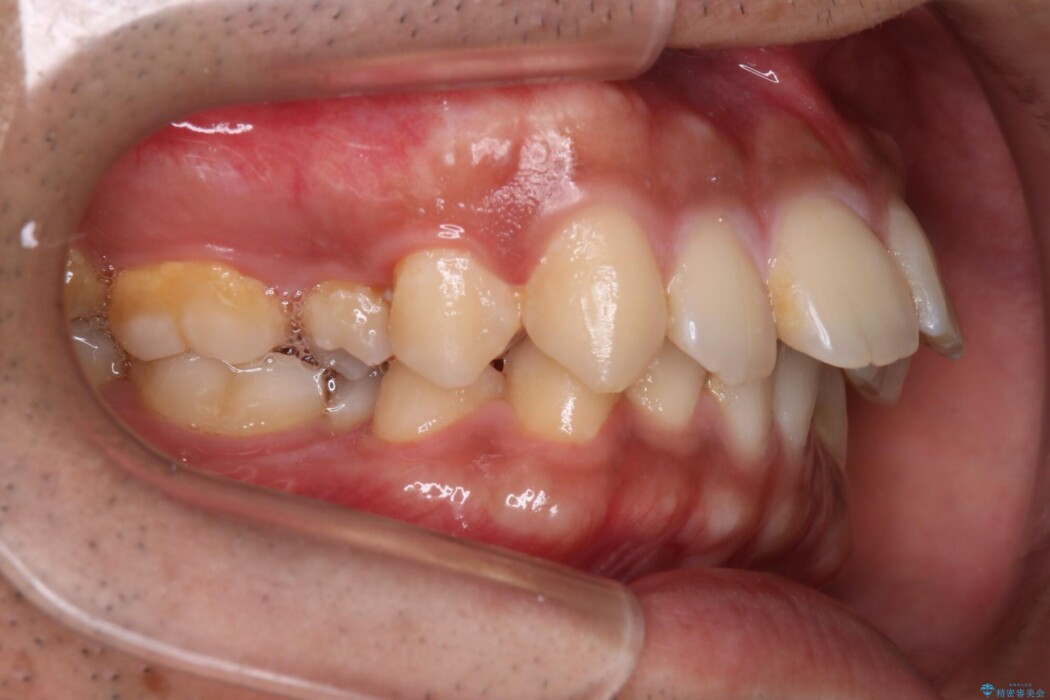

重度の叢生を審美ワイヤー装置で整える

歯列のガタガタさをなおしたいとのことで来院されました。

比較的重度の叢生であり整えるためのスペースが足りなかったため抜歯を行うことで確保し、ワイヤー装置にて配列を行いました。

特に奥歯の捻転がひどく、整った歯列となるまでに時間は要しましたが、きれいな仕上がりに患者様には大変ご満足いただけました。